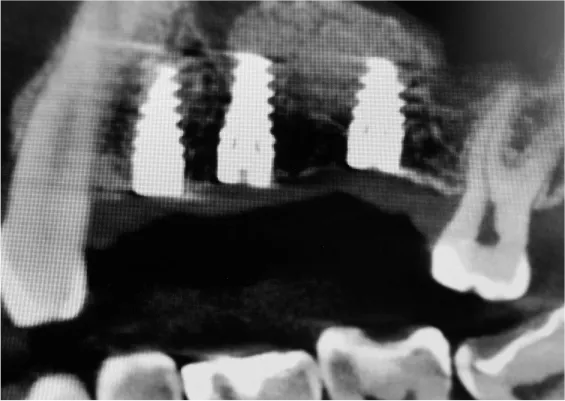

ZABIEGI REGENERACJI KOSTNEJ WOKÓŁ WSZCZEPIANYCH IMPLANTÓW

Sterowana regeneracja kości GBR przy użyciu biomateriałów oraz membran zaporowych. Procedury te są stosowane w sytuacji niedostatecznej ilości kości, skutkującej odsłonięciem gwintu, podczas gdy wszczepiamy implanty stomatolo-giczne lub też jako zabiegi poprzedzające ich wprowadzenie.

Metoda rekonstrukcji kostnej w oparciu o indywidualnie drukowane siatki z tytanu dla implantacji wszczepów śródkostnych stosowana jest najczęściej jako dwuetapowa. W pierwszym etapie odbudowywana jest kość, natomiast implanty wszczepiane są po okresie 4–6 miesięcy. Na wgojenie implantów oczekujemy od 4 do 6 miesięcy w zależności od miejsca ich lokalizacji. Siatka tytanowa po spełnieniu swojej funkcji rusztowania dla odbudowującej się kości jest następnie usuwana w dniu wszczepienia implantu. Jeżeli kość spełnia odpowiednie warunki, istnieje możliwość zastosowania modyfikacji siatki tytanowej, która umożliwia jednoczesne wprowadzenie implantów wraz z odbudową kostną.

Wariant ten skraca czas od pierwszego zabiegu do wykonania gotowych koron protetycznych na wprowadzonych implantach. Opisane schematy procedur regeneracyjnych wykazują znaczną innowacyjność, jeśli chodzi o wykorzystanie technologii cyfrowej w medycynie odtwórczej. Natomiast w codziennej praktyce chirurgicznej poprawiają precyzję, tempo oraz przewidywalność w świadczeniu usług polegających na odbudowie zniszczonych lub zdeformowanych ludzkich tkanek.